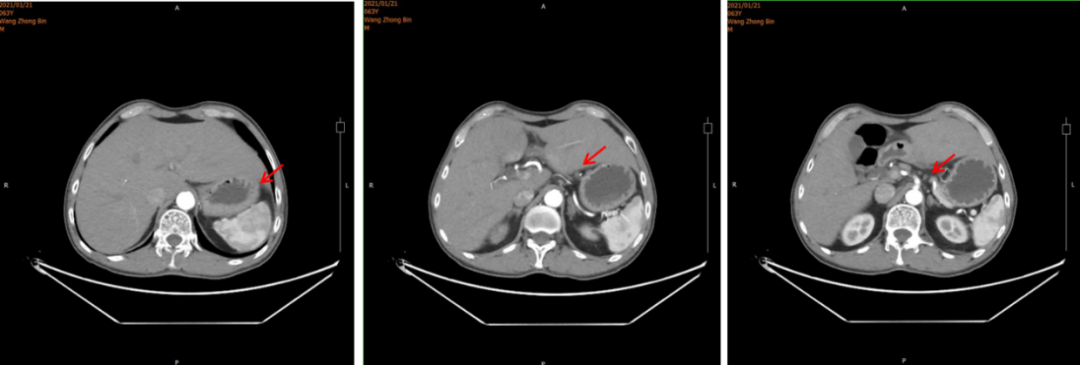

2021年5月12日、7月21日和12月28日:上腹部MRI示:肝、胃术后改变,肝左叶环形强化影,体积较前逐渐减小(最大径分别为15.8mm、14.8mm、10.6mm)。(图5)

图5.上腹部MRI

PR

汉曲优®Ⅲ期临床研究[3]结果显示,汉曲优®与原研曲妥珠单抗疗效等效,安全性、免疫原性相似,曲妥珠单抗生物类似药得到NCCN-GI指南、CSCO-GI指南的用药推荐,2020年《中国生物类似药专家共识》也指出:生物类似药与参照药疗效等同、安全性相似,临床上可以替代使用。在本病例中,患者综合经济因素等原因,在使用原研曲妥珠单抗7周期有效后,转换为曲妥珠单抗生物类似药(汉曲优®)继续治疗,目前已使用10周期,并于2021年12月28日复查上腹部MRI示:肝、胃术后改变,肝左叶环形强化影,体积较前逐渐减小,达到PR,显示出良好的疗效和安全性。